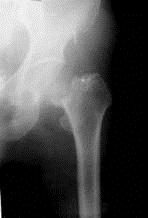

病历摘要: 患者××,女性,70岁,不慎跌倒致伤左髋部后疼痛、活动障碍2天。查体:左下肢呈屈髋屈膝及外旋畸形,右下肢活动时左髋部疼痛,左足跟和大粗隆有叩击...

问题 病历摘要: 患者××,女性,70岁,不慎跌倒致伤左髋部后疼痛、活动障碍2天。查体:左下肢呈屈髋屈膝及外旋畸形,右下肢活动时左髋部疼痛,左足跟和大粗隆有叩击痛。 人工髋关节置换术后的并发症是:

选项 A、股动静脉损伤 B、坐骨神经损伤 C、肺栓塞 D、伤口感染 E、深部静脉栓塞 F、人工关节置换术后股骨骨折 G、异位骨化 H、假体松动 I、人工关节脱位 J、腓骨神经损伤

答案 ABCDEFGHIJ